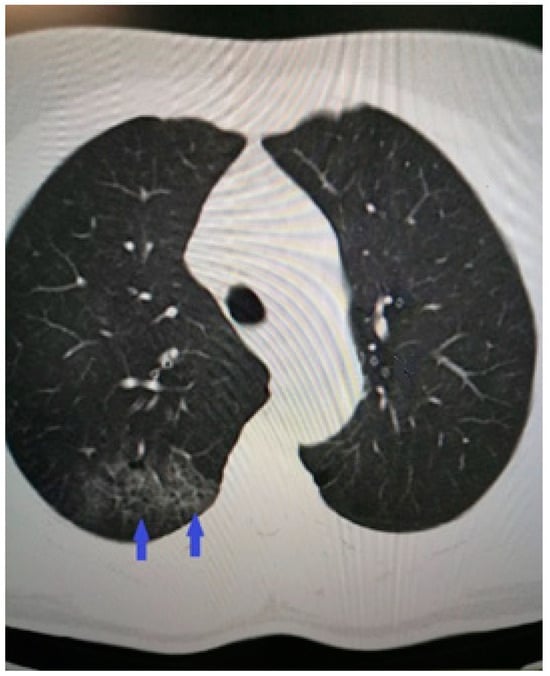

The diagnostic process continued with imaging studies. The computed tomography revealed right-sided pneumonia with COVID-19-typical ground-glass opacities and interlobular septal thickening (Figure 2).

Figure 2.

Chest CT showing peripheral right-sided consolidations and parenchymal ground-glass opacities consistent with COVID-19 pneumonia.